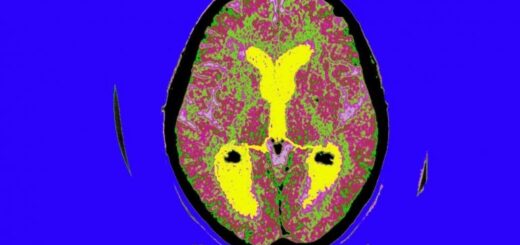

«Σε αυτή τη μελέτη επικεντρωθήκαμε σε μια περιοχή του εγκεφάλου που ονομάζεται τοξοειδής πυρήνας του υποθαλάμου, ο οποίος είναι ο κύριος ρυθμιστής της πρόσληψης τροφής, της σωματικής δραστηριότητας και του μεταβολισμού», είπε ο πρώτος συγγραφέας Harry MacKay. «Ανακαλύψαμε ότι ο τοξοειδής πυρήνας υφίσταται εκτεταμένη επιγενετική ωρίμανση κατά τη διάρκεια της πρώιμης μεταγεννητικής ζωής. Αυτή η περίοδος είναι επίσης εξαιρετικά ευαίσθητη στον αναπτυξιακό προγραμματισμό της ρύθμισης του σωματικού βάρους, υποδηλώνοντας ότι αυτά τα αποτελέσματα θα μπορούσαν να είναι συνέπεια της απορρυθμισμένης επιγενετικής ωρίμανσης».

Η ερευνητική ομάδα διεξήγαγε αναλύσεις σε όλο το γονιδίωμα τόσο της μεθυλίωσης του DNA -μια σημαντική επιγενετική ετικέτα- όσο και της γονιδιακής έκφρασης, τόσο πριν όσο και μετά το κλείσιμο του μεταγεννητικού κρίσιμου παραθύρου για τον αναπτυξιακό προγραμματισμό του σωματικού βάρους. «Ένα από τα μεγαλύτερα πλεονεκτήματα της μελέτης μας είναι ότι εξετάσαμε τις δύο κύριες κατηγορίες εγκεφαλικών κυττάρων, τους νευρώνες και τα γλοιακά κύτταρα», είπε ο MacKay.